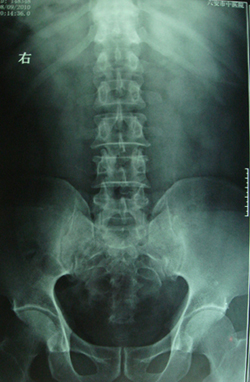

典型病例,男,56岁。无痛性血尿3月。

膀胱占位性病变,呈菜花状生长,考虑膀胱癌。 期待病理。